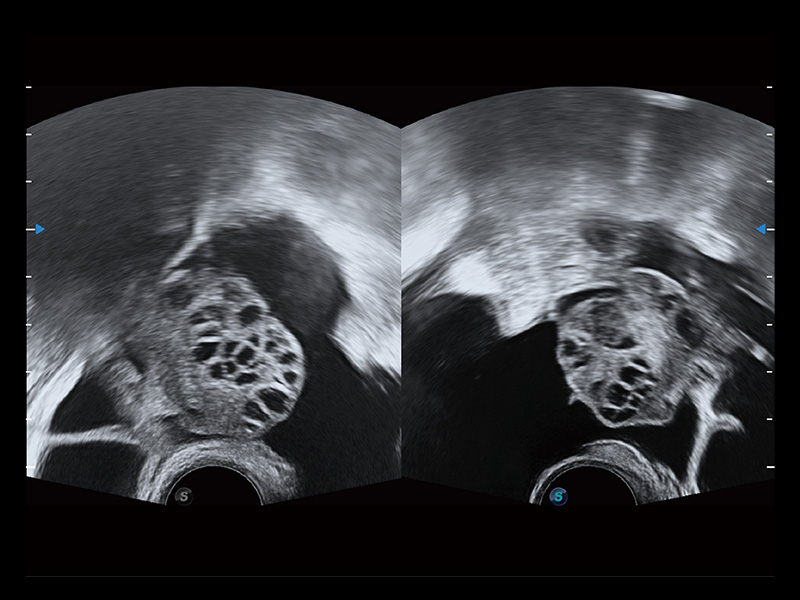

“生育问题”即关系民族复兴,也关系亿万家庭的幸福。随着婚育年龄推迟、社会压力增加等因素,越来越多人群也面临着“生不出、生不好”的问题。辅助生殖作为治疗不孕不育最有效的方法之一,也逐渐成为育儿新希望。而超声检查能为生殖需求人群的初诊评估提供宝贵的信息。 P20 Elite是开立医疗匠心打造的一款生殖应用型彩超。她继承开立医疗高端极光平台,突破性地将多款新型芯片及硬件模块进行整合,均衡了高端系统性能与小巧灵动机身。P20 Elite卓越的图像质量搭载专科探头,旨在为您提供全面的辅助生殖解决方案。

P20 Elite配备了丰富的生殖探头群和临床应用功能,在卵泡监测、穿刺取卵、胚胎移植、妊娠确认等领域,为生殖需求人群提供了新的临床机会,重新定义高端超声如何应用于生殖健康检查。